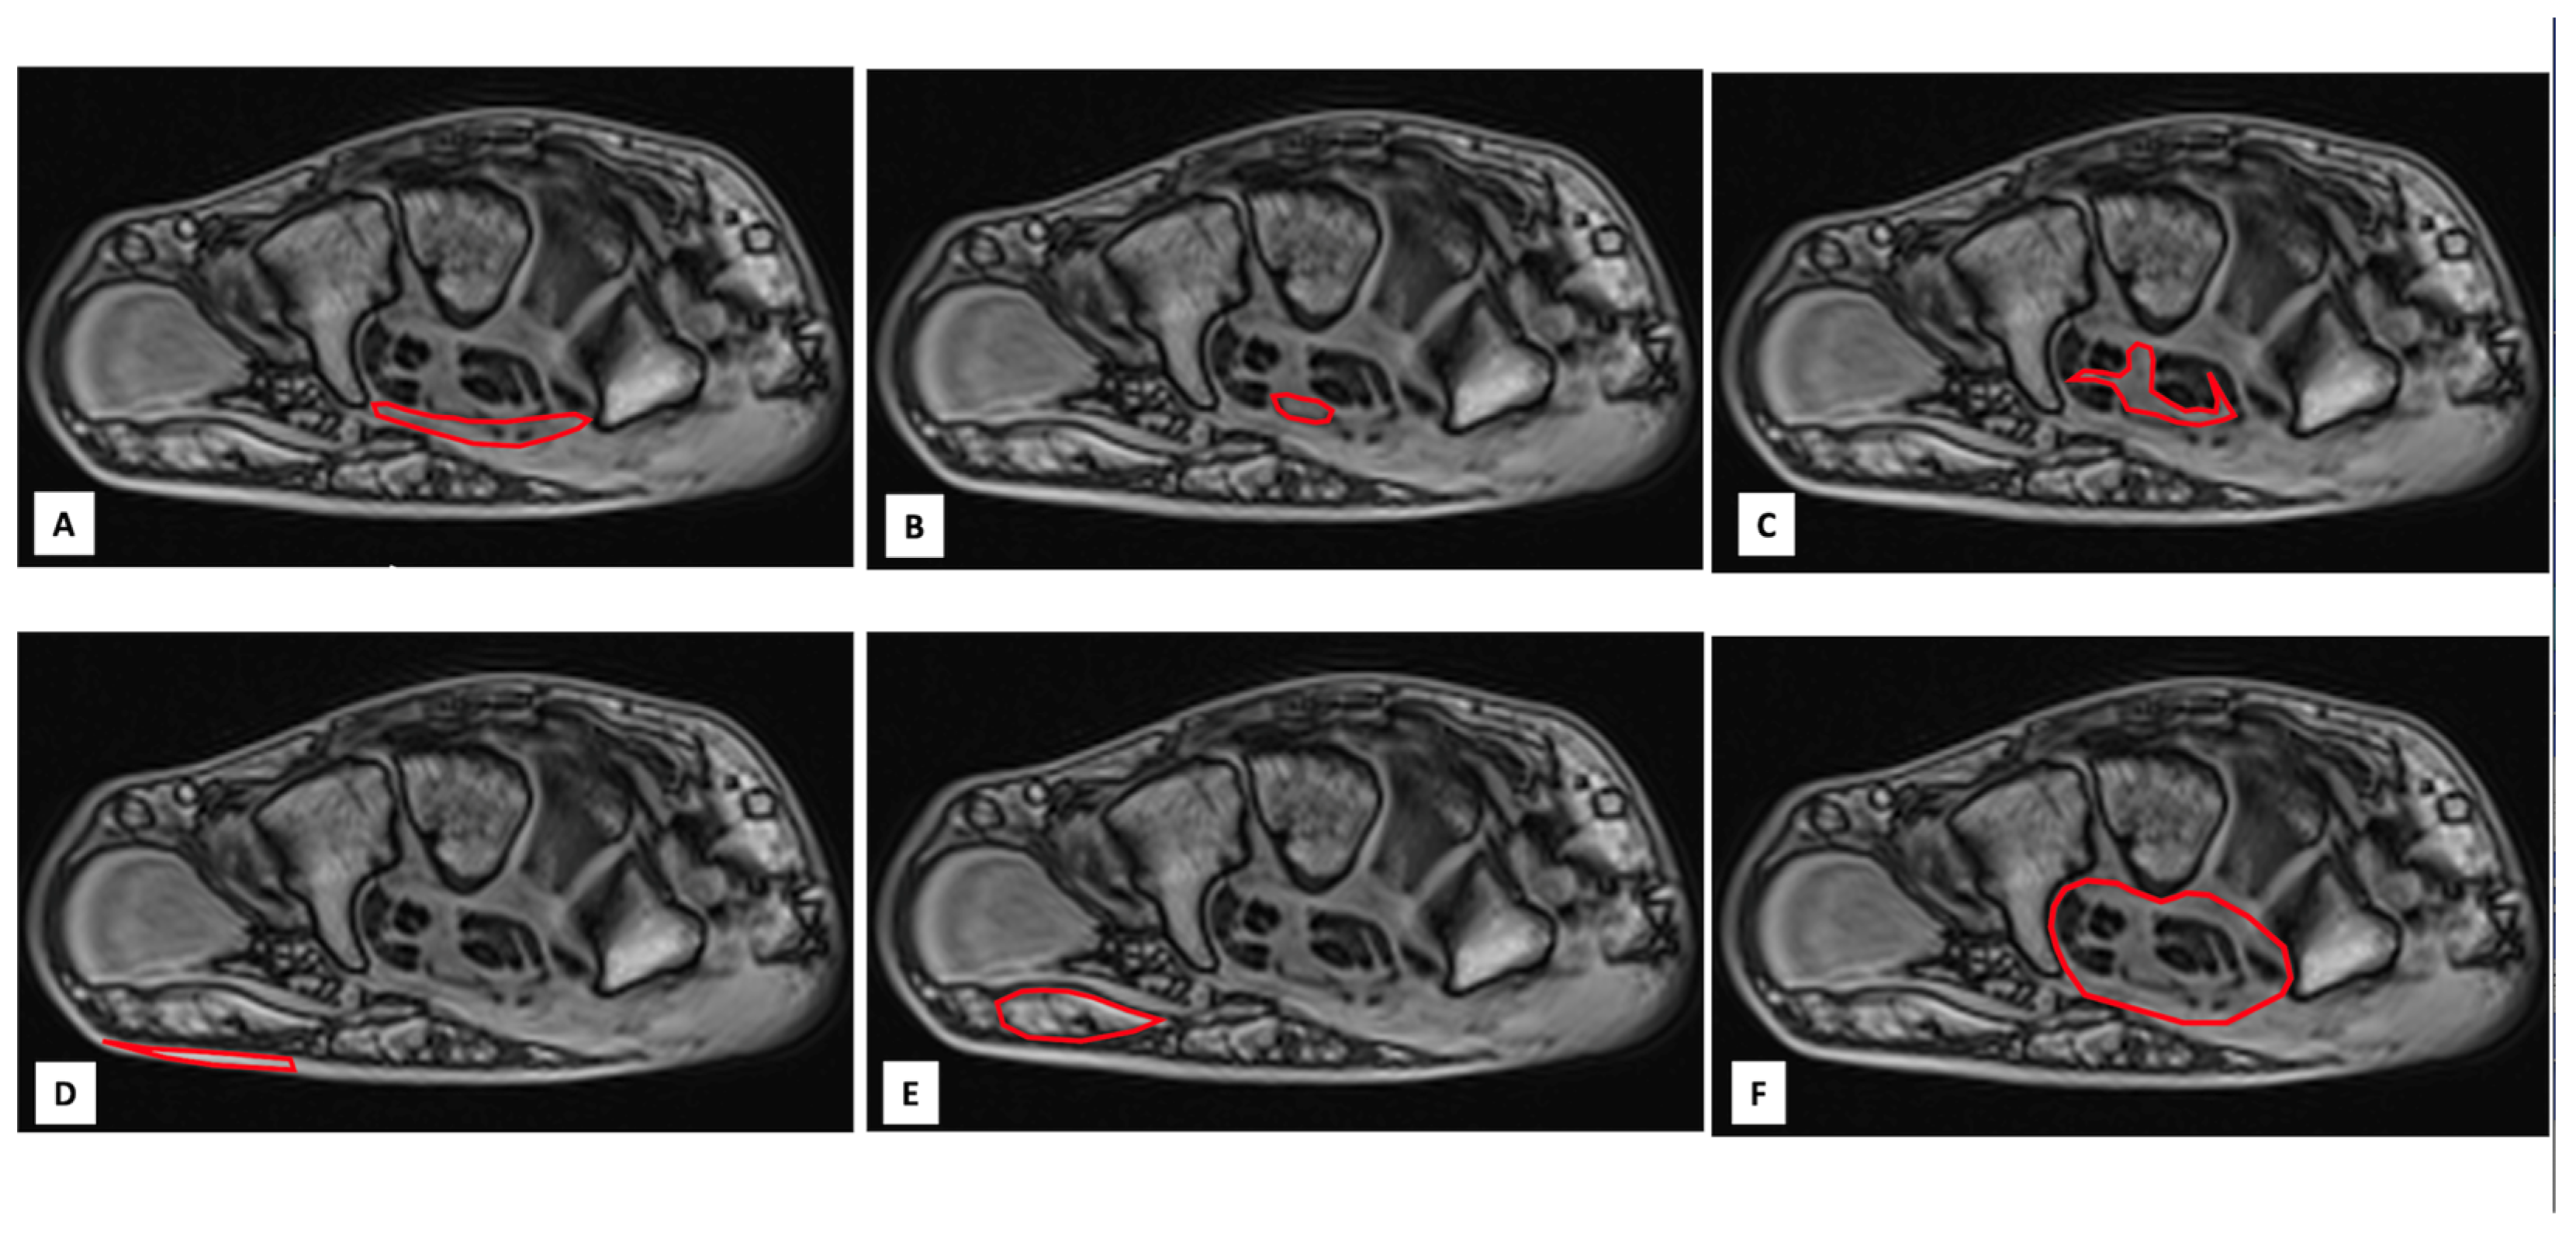

2.4. Image Analysis

Image analysis was performed by consensus of 2 authors (RC, JFD). A visual analysis of the MRI images, looking for an abnormal mass at the level of the carpus, suggesting amyloid deposits, was first performed by the authors. In a second step, the following 5 anatomical structures of the wrist, classically involved in CTS, were manually contoured by consensus of 2 authors (RC, JFD) from axial 2 degrees flip angle gradient echo images at 3 levels of the wrist (proximal, middle and distal levels): the transverse carpal ligament (TCL), the median nerve (MN), the sheaths of the flexor carpi tendons (SFCT), the subcutaneous fat of the wrist (SCF) and the muscle of the thenar eminence (MTE). A sixth measurement consisting of a global contouring of the wrist (GCW) encompassing all the above-mentioned structures was also performed (Figure 3). The 6 contours for each slice level were then copied onto the gradient echo images acquired with the other flip angles. Manual adjustment of the contours was performed in case of a shift between the images. In case of difficulties in finding the boundaries of the above-mentioned structures on gradient echo images, the operators used the images of the proton density spin echo sequence. The signal intensities (SI) of all analyzed structures were noted for each flip angle and for each measurement plane. The SI values obtained at the 3 levels of the wrist were averaged. Thus, 6 mean SI values (one for each flip angle) were obtained for each structure. The native T1 value of each structure was then calculated from these 6 values using a previously reported method [25].

Figure 3. Examples of manually contouring (red line) of transverse carpal ligament (TCL) (A), median nerve (MN) (B), sheaths of the flexor carpi tendons (SFCT) (C), subcutaneous fat of the wrist (SCF) (D) and muscle of thenar eminence (MTE) (E) at the proximal level of the wrist on axial gradient echo images. The sixth measure (F) consisted of a global contouring of the wrist (GCW) encompassing all the above-mentioned structures.